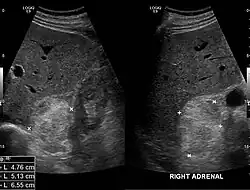

Myelolipome sind gelbe bis bräunliche, wenige Millimeter bis 30 cm große, umschriebene, jedoch nicht gekapselte Tumoren. Sie treten üblicherweise solitär und einseitig im Bereich einer Nebenniere auf, werden selten jedoch auch bilateral und/oder außerhalb der Nebenniere (z. B. im Retroperitoneum, Mediastinum, der Leber, in Muskelfaszien) gefunden. Mikroskopisch setzt sich der Tumor aus reifem Fettgewebe und myeloiden Zellen zusammen. Gelegentlich werden Infarktareale, Einblutungen oder knöcherne Metaplasien beobachtet.[1][2]

Die Mehrzahl der Myelolipome sind asymptomatisch und werden zufällig, etwa im Rahmen radiologischer Untersuchungen oder einer Obduktion gefunden. Nur gelegentlich, insbesondere bei größeren Tumoren, berichten betroffene Patienten von Bauch- oder Flankenschmerz. Selten bestehen endokrine Störungen wie das Cushing-, Conn-Syndrom oder eine angeborene Nebennierenhyperplasie.[1]